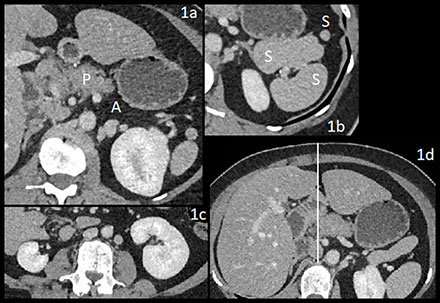

CT showed dorsal pancreatic (P) agenesis (A) (Figure 1a).

– Four spleens (S), one adjacent to the stomach (Figure 1b).

– Right renal hypotrophy (Figure 1c).

– Midline falciform ligament (Figure 1d).